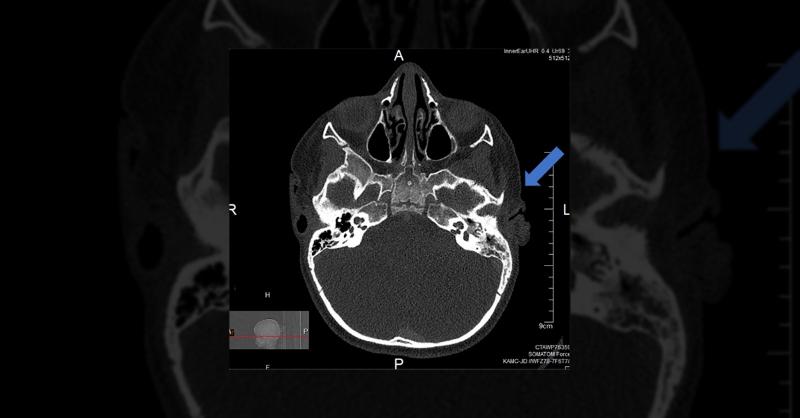

A 3-year-old boy was presented with delayed speech development and hearing impairment since age one, primarily due to congenital glaucoma surgically managed. Comprehensive evaluations such as cardiological, behavioral, and developmental—indicated no concerning findings except for bilateral sensorineural hearing loss necessitating hearing aids. An a

Management of Foreign Body Complication in Middle Ear